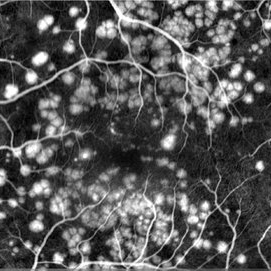

Birdshot Retinopathy

Female patient, 41 years old, with progressive low visual acuity, progressive history of autoimmune disease. In the multimodal retinal fundoscopic evaluation, important characteristics compatible with "Birdshot Retinopathy" were observed. Birdshot retinopathy, also known as birdshot chorioretinopathy or birdshot uveitis, is a rare, chronic inflammatory disorder that affects the retina and the choroid of the eye. It typically develops in adults between the ages of 30 and 60 years, and is more common in women than men. The name "birdshot" refers to the small, round, yellow-white spots that appear on the retina, which resemble the pattern of a shotgun blast. These spots are caused by inflammation in the eye, and can lead to vision loss if left untreated. Symptoms of birdshot retinopathy include blurred vision, floaters, loss of night vision, and difficulty adapting to changes in lighting. The condition can also cause inflammation in other parts of the eye, leading to redness, pain, and sensitivity to light. The exact cause of birdshot retinopathy is unknown, but it is believed to be an autoimmune disorder, in which the body's immune system mistakenly attacks the retina and choroid. Treatment typically involves the use of immunosuppressive medications, such as corticosteroids or biologic agents, to reduce inflammation and preserve vision. Close monitoring by an ophthalmologist is important, as the disease can progress even with.

Photographer: JEFFERSON ROCHA DE SOUSA - Retinal Department at Institute Dr. Suel Abujamra Sao Paulo-Brazil

Imaging device: Clarus 700 - Zeiss, composition of five 135 degree images.

Condition/keywords: bilateral chorioretinal folds, birdshot, birdshot chorioretinopathy, birdshot choroidopathy, birdshot retinochoroidopathy